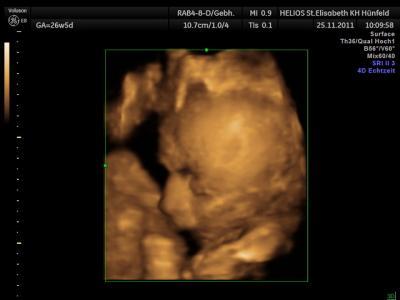

Bild zu komische Gedanken - Forum für Februar - Mamis